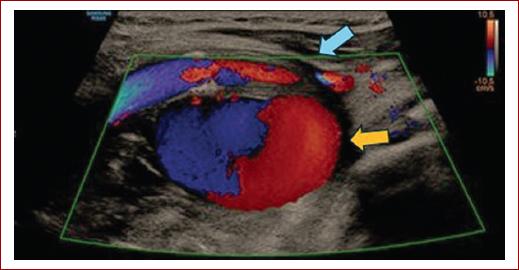

De acuerdo con estos hallazgos, en un primer momento se plantearon como posibles diagnósticos un glomus o un aneurisma carotídeo, por lo que se realizó una ecografía Doppler que confirmaba la presencia de una dilatación aneurismática sacular de 30 milímetros de diámetro en la cara posterior de la bifurcación carotídea izquierda con un patrón de color y flujo en ida y vuelta (signo de «yin-yang») (Fig. 3).

Figura 3 Imagen de aneurisma con flujo bidireccional con signo de ying-yang en ecografía Doppler (flecha amarilla) dependiente de bifurcación carotídea (flecha azul).

Cuando la imagen obtenida en la angio-TC es dudosa y plantea un diagnóstico diferencial con masas sólidas, la captación de flujo con la modalidad Doppler color nos confirma el diagnóstico. Por ello, la ecografía Doppler debe ser la prueba de imagen inicial y posteriormente realizar otras pruebas de imagen de cara a planificar el tratamiento4,10,11.